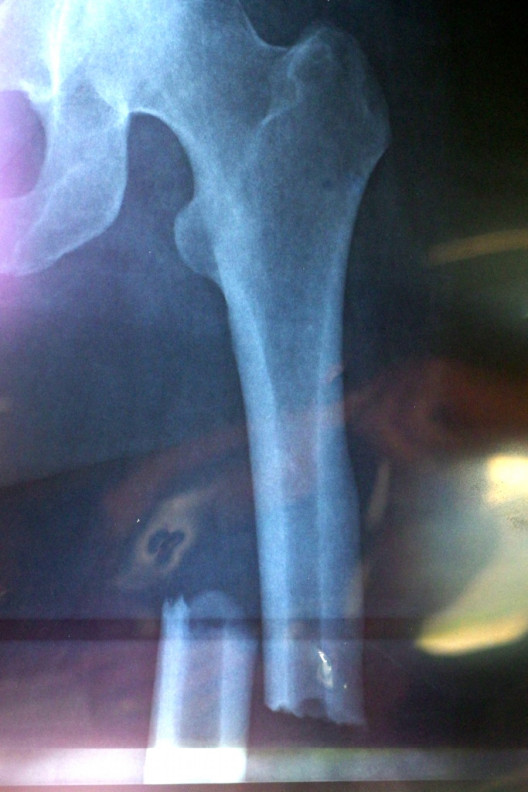

” No not at all. I feel completely validated and fully diagnosed. My broken pathological femur xray alone is absolute evidence of my disease, along with my multiple fractures throughout my body, my “art gallery” of xrays, MRIs, bone scans all showing bone disease activity and my low bone turnover blood tests and my high bone density scans. My body screams rare bone disease at every corner”

My medical team are still trying to investigate my case. They want to try and slow the progression of my disease, if possible. We also know the type of disease I have and the pathological pattern it’s following. On some scans it has a malignant pattern involving my bone marrow. It doesn’t mean it’s cancer but it has the same components on MRIs. It’s why I occasionally have a Hematologist/Oncologist on my team.

You may remember while I was in Hospital late last year, my Drs organised a bone biopsy from my hip to be sent to a world renowned bone Specialist based in Sydney. He specialises in metabolic bone diseases.

The week before Christmas I finally got the result…..severe bone disease with low bone turnover but unexpectedly he said the bones were soft, not hard.

They have always been hard on none density scans and it’s how my Surgeons have found them when they have been operating on my fractures. Also when you have low bone turnover, the bone disease generally does have hard bone not soft bone.

This led my Endocrinologist to ask me to have a fresh Bone Density Scan, which I managed to do 2 weeks ago. She wanted these results to be able to discuss my case further with the Professor analyzing my bone biopsy.

The Bone Density Scan still showed high bone density!